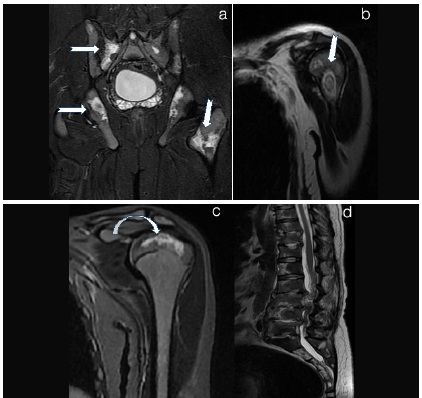

Bone marrow and soft tissue oedema a) Tibia and Femur Coronal b) Axial Tibia a) STIR image Extensive bone marrow oedema (star in b) in tibia with surrounding soft tissue hyperintensity (arrows in b) suggesting soft tissue oedema. b) Axial STIR tibia shows increased signal in medulla of tibia and surrounding soft tissues suggesting marrow oedema

Infective arthritis of hip joint a)T1WI b)T2WI c)STIR

a) Coronal T1WI show cortical erosions of right acetabulum and subarticular region of right femoral headwith reduced joint space (thin arrow in a). b) Axial T2WI show minimal right hip joint effusion with cortical erosion and marrow oedema in pariarticular region. C) Axial STIR image shows extensive high signal intensity areas in head of femur and acetabulum with surrounding soft tissues showing abnormal high signal intensity and reduced joint space on right side suggesting bone marrow and soft tissue oedema (arrow in c). This was suggestive of arthritis and was proven to be of Tubercular aetiology on cytology